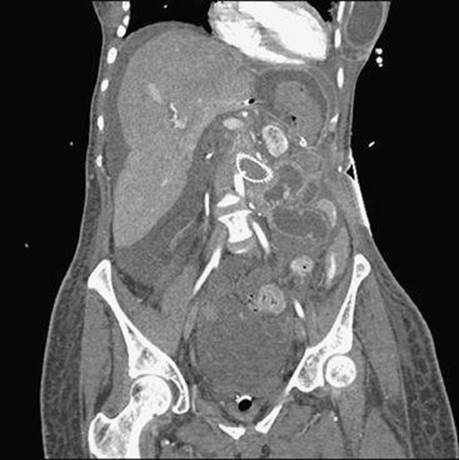

A 63-year-old “vasculopath” presents with massive GI bleeding about 6 weeks after another episode of bleeding during which an esophagogastroduodenoscopy (EGD) and colonoscopy were normal. An emergent CT scan is obtained. What is the diagnosis?

Figure 1-4

An aorto-enteric fistula. The so-called “herald bleeding episode,” in which significant bleeding that spontaneously ceases occurs, is characteristic of this condition. Although CT scan is more sensitive than endoscopy to diagnose this condition, the sensitivity of CT is still relatively low. This diagnosis, therefore, requires a high index of clinical suspicion. Endoscopy is often necessary to exclude a peptic process as a cause of the bleed but should be done in conjunction with surgery.